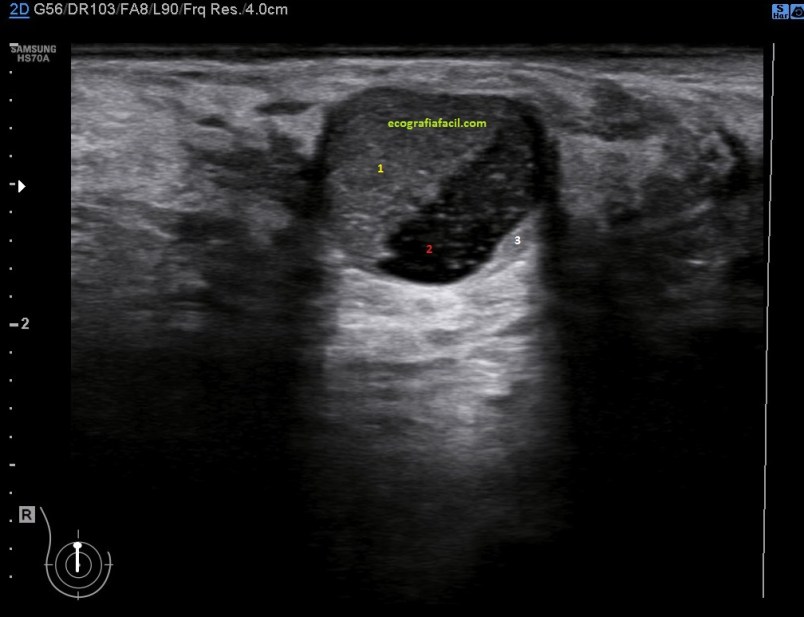

Cambian su aspecto de este modo, normalmente son anecoicos siempre, luego empiezan a cambiar hasta que son mitad anecoicos, mitad ecogénicos, como la imagen 2 y luego son totalmente ecogénicos como el quiste ecogénico de la foto 1.

En esta imagen 2 ves un nódulo quístico, mitad ecogénico marcado con un 1 en amarillo y mitad anecoico marcado con un 2 en rojo.

La radióloga puede tener dudas en algunas exploraciones, si por ejemplo es la primera exploración que se realiza la paciente apareciese este tipo de lesiones, entonces determinará ampliar con un estudio mediante intervencionismo o bien con control ecográfico, en este caso, no hizo falta pinchar el nódulo, vimos a ese quiste envejecer durante los controles que la paciente se realizaba regularmente y vimos cómo cambió de anecoico a hiperecogénico paulatina y lentamente año tras año, control tras control, primero siendo anecoico, luego parcialmente ecogénico y finalemente ecogénico por completo, siempre del mismo tamaño y colocado en la misma posición, por eso, en este caso no requirió análisis de Anatomía Patológica.